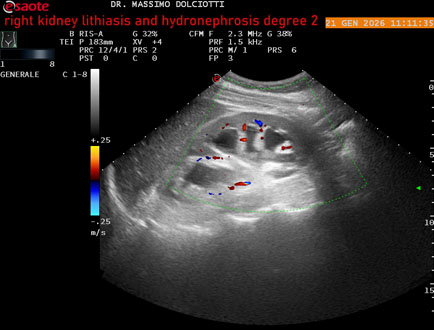

Data inserimento: 22/01/2026

Ecografia del: 21/01/2025

Strumento: Esaote MyLab Eight

Sonda: Convex Multifrequenza 1-8 MHz

Età Paziente: M 27 anni

Motivazione dell'esame: dolore al fianco destro da 3 mesi.

Commento all'esame: le immagini ed il video documentano il rene destro in sede, con ecostruttura disomogenea per evidenza, alla pelvi renale, di immagine iperecogena delle dimensioni di 16,2 mm, con cono d'ombra posteriore, da ricondurre a litiasi ed una formazione simile, di minore entità, al polo inferiore, delle dimensioni di 6,8 mm. Rene dx con diametro longitudinale di 122 mm (v.n. 90-120 mm) x 63 mm e parenchima renale dello spessore di 15 mm (v.n. > 13 mm). Rene dx con idronefrosi di 2° grado.

Conclusioni: litiasi e idronefrosi di 2° grado al rene destro (lithiasis and second-degree hydronephrosis of the right kidney).

In collaborazione: Dr.ssa Marica Manfredi - Ancona, Dr. Ilir Qose - Ancona

Presentazione: Dr. Massimo Dolciotti - Ancona

Elaborazione digitale: Andrea Dini - Ancona